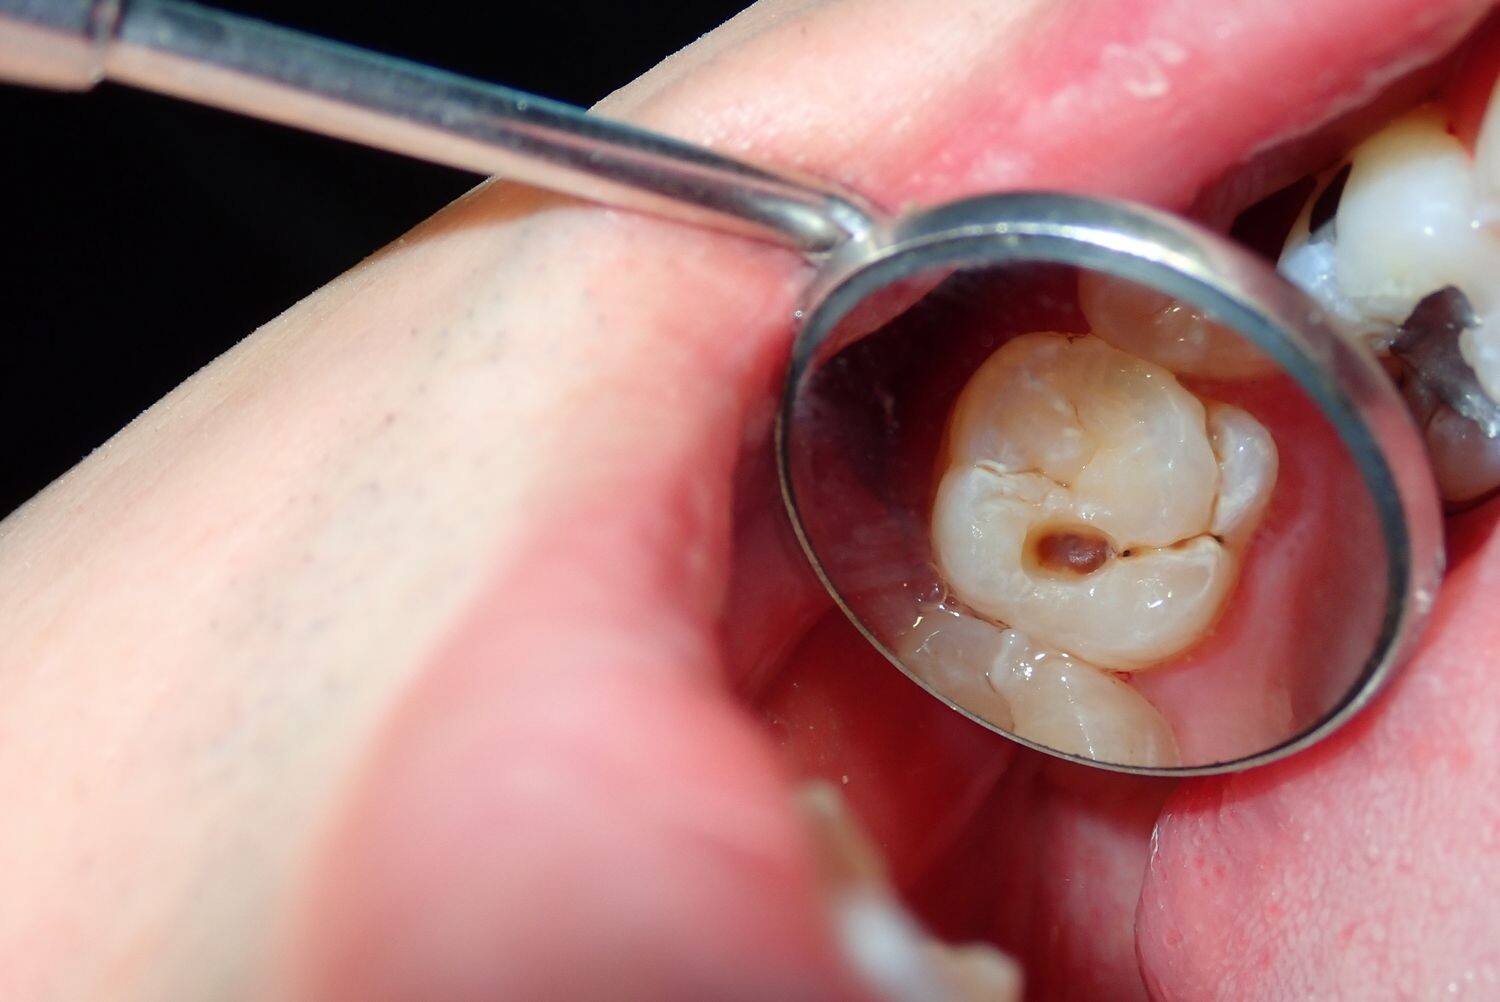

Signs of a Cavity

What does a cavity feel like? In the earliest stages, the answer might be nothing. There are no nerves in your tooth enamel, so when the decay is in that layer, you likely won't feel a thing. Once the decay has progressed enough to reach the softer tissues inside the tooth, where the dentin and nerves are, you might notice signs of a cavity. Your teeth might feel sensitive and you could feel some pain, especially after eating sweets, hot foods or cold foods. The pain can be fairly mild or sharp and intense. Some people with cavities also feel pain when biting down.

Depending on the size of the cavity, you may be able to see evidence of it in your mouth. Cavities sometimes create visible holes in the teeth. They can also create stains that are black, brown or white on the surface of the tooth.

What should you do if you think you have a cavity? The first step is to see your dentist. Although cavities can be reversed in the early stages, by the time you are feeling discomfort or pain, only a dentist can treat them. An x-ray will be taken to determine how the cavity has progressed into the tooth. Depending on how severe the cavity is, you might need a filling to fix it. If the decay is very severe, the dentist might replace the tooth with a crown or perform a root canal.

Even if you're not sure if you have a cavity, regular professional cleaning and dental visits are important. A dental hygienist can apply a fluoride treatment to help strengthen the teeth and reverse the very early stages of decay. He or she can also give you tips on the best ways to brush your teeth and advise you about what foods to avoid or consume less frequently to reduce your risk for cavities. As with many conditions, when it comes to cavities, taking preventative steps is a lot easier than treating the problem down the road.